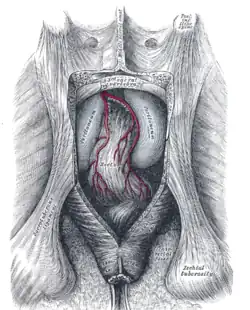

Muscles of the female perineum The posterior aspect of the rectum and anus exposed by removing the lower part of the sacrum and the coccyx

The posterior aspect of the rectum and anus exposed by removing the lower part of the sacrum and the coccyx